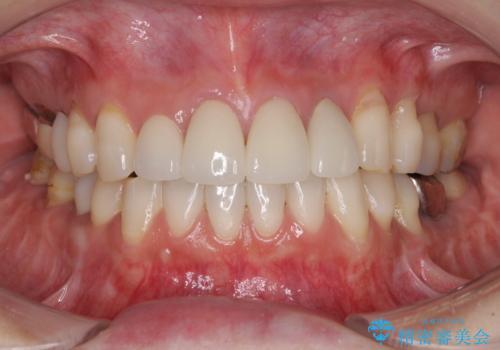

以前矯正治療をされ、その時には歯列が整ったので満足されたそうですが、若干の後戻りにより隙間ができ、矯正治療前に治療していた虫歯の跡が気になったため、オールセラミックによる審美治療を希望されました。

目立つ範囲である前歯4歯をオールセラミッククラウンにて補綴することとしました。

口元の印象が明るくなり、人前で気にせずに笑えるようになりました。